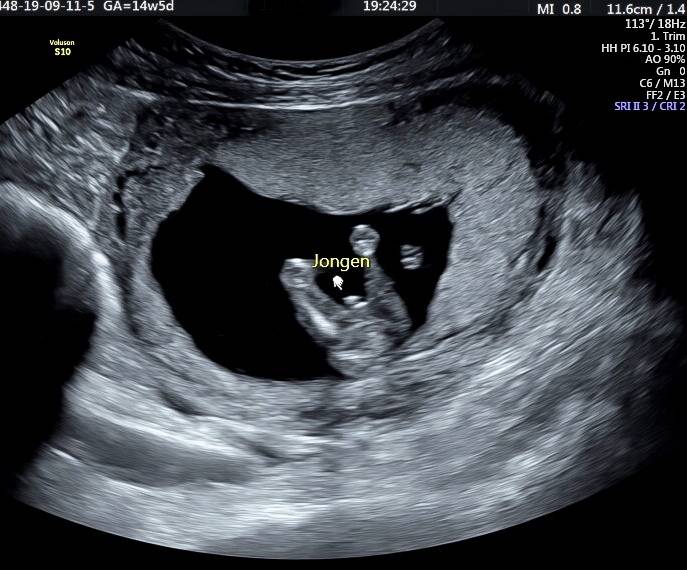

Wij maken jouw kennismaking magisch

Zwanger zijn is iets magisch. En dat prachtige gevoel willen wij nastreven in onze praktijk. Onze echoscopisten hebben een verloskundig achtergrond en werken daarnaast met de beste apparatuur. Ook hebben wij de leukste samenwerkingen met de mooiste merken waar jullie van kunnen profiteren. Dit alles zorgt voor een geweldige ervaring. Tot snel bij Baby Glimpse…